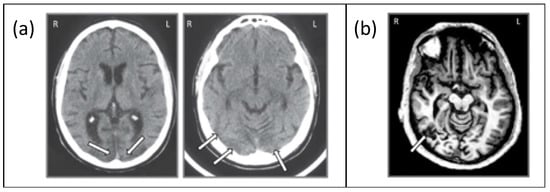

2.1. Participants